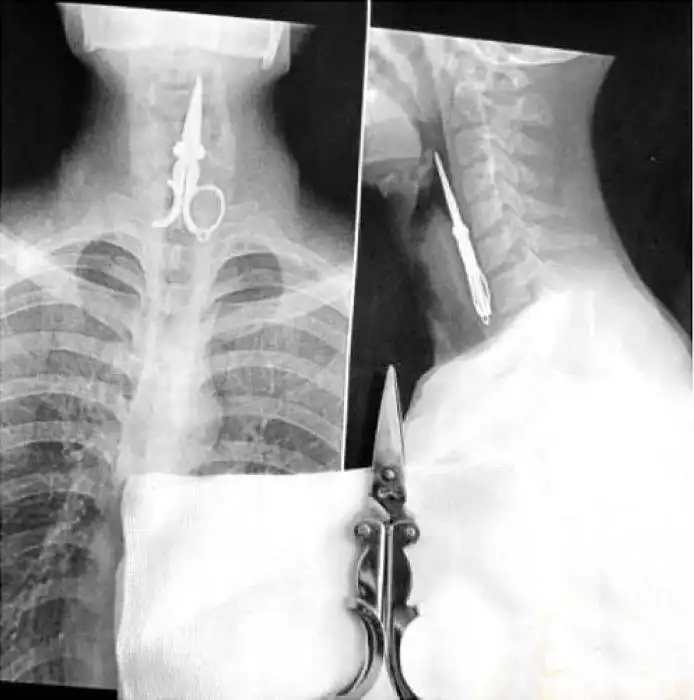

Необычные предметы в теле людей на рентгеновских снимках

На рентгеновских снимках людей порой можно обнаружить самые необычные предметы, которые находятся в их теле.

Человечество явно с гвоздями не дружит!!! Что не снимок то гвоздь в башке!